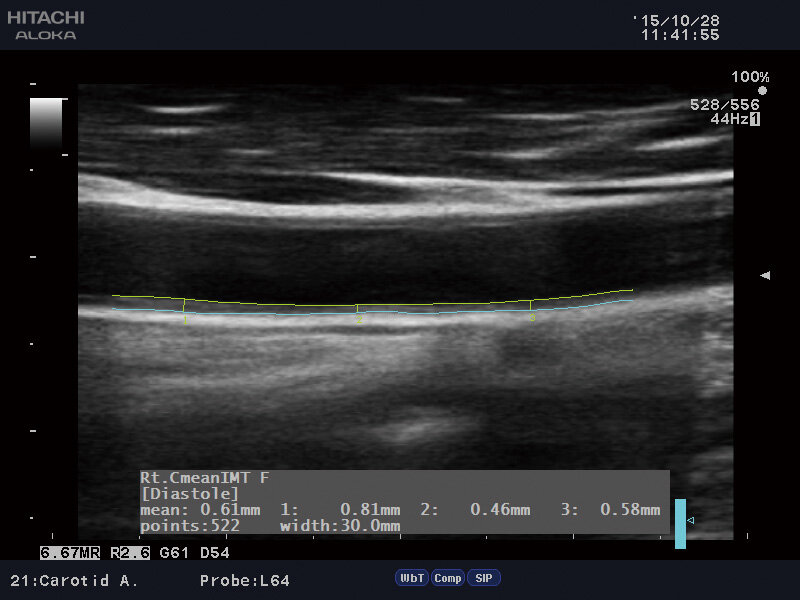

Если сдать кровь на холестерин - мы можем узнать, что он повышен, вот только мы не будем знать как дела у наших сосудов - есть ди там бляшки, мешают ли они току крови и т.д. Да, существует такая диагностика, как ангиография, но для нее есть особые показания, всем ее не делают. Но есть другой способ узнать о проблемах в коронарных артериях - это сделать УЗИ сосудов шеи (ЭКДС) с расчетом толщины "комплекс интима-медиа" (КИМ). Интима сосудов — это внутренняя часть артерий, которая выстилает внутреннюю полость. Её толщина — показатель возраста сосудов. Также она косвенно показывает нам о том, что там есть холестериновые бляшки. Интересно, что увеличение толщины КИМ сонной артерии всего на 0,1 мм статистически значимо увеличивает риск инфаркта сердца на 15%, а риск инсульта мозга на 18% с учетом поправок на возраст и пол. А ведь это основные причины смерти.

Теперь перейдем к цифрам:

В норме толщина комлекса интима-медиа 0,9+0,1 мм!

Если толщина выше - это значит в сосудах сердца, вероятнее всего имеются холестериновые бляшки и уже необходимо предпринимать меры по их лечению